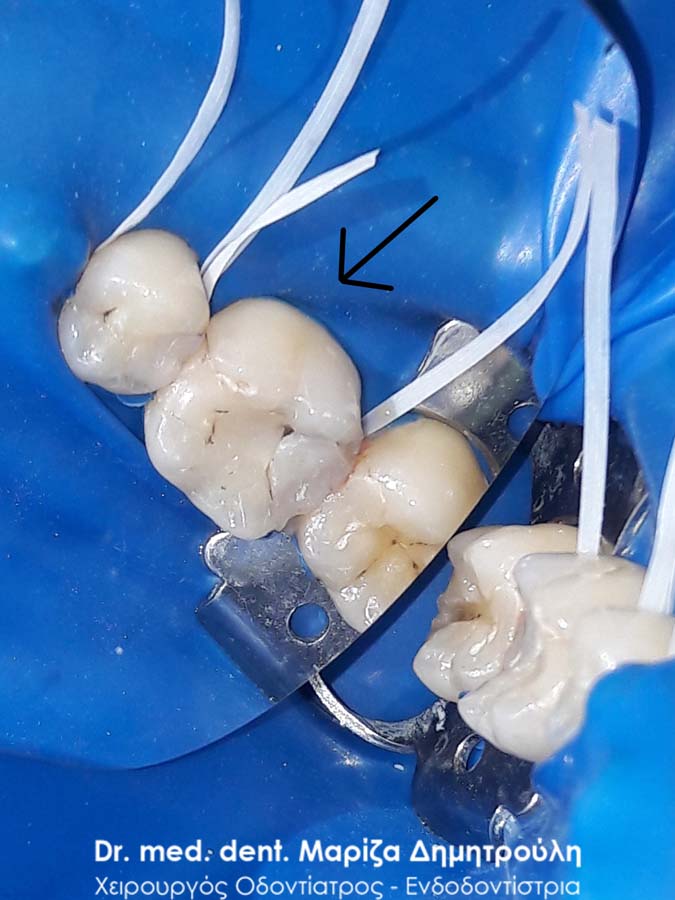

Εικόνα των δοντιών με τη χρήση ελαστικού απομονωτήρα

Η θεραπεία πραγματοποιήθηκε με τη χρήση ελαστικού απομονωτήρα, όπως ορίζουν τα παγκόσμια πρωτόκολλα οδοντιατρικής για την αφαίρεση των μαύρων σφραγισμάτων. Οι οδοντίατροι θα ήταν καλό να χρησιμοποιούν απομονωτήτρα κατά την αφαίρεση σφραγισμάτων αμαλγάματος, έτσι ώστε ο ασθενής να εισπνέει ελάχιστα και να μην καταπίνει τον υδράργυρο, που απελευθερώνεται κατά τη διαδικασία αυτή.

Ο ασθενής επιθυμούσε την αντικατάσταση των μαύρων σφραγισμάτων αμαλγάματος στον πρώτο δεξιό γομφίο και στο δεύτερο γομφίο με λευκά σφραγίσματα σύνθετης ρητίνης. Η θεραπεία πραγματοποιήθηκε με τη χρήση ελαστικού απομονωτήρα, όπως ορίζουν τα παγκόσμια πρωτόκολλα οδοντιατρικής για την αφαίρεση των μαύρων σφραγισμάτων. Όταν οι οδοντίατροι χρησιμοποιούν απομονωτήτρα κατά την αφαίρεση σφραγισμάτων αμαλγάματος, τότε ο ασθενής εισπνέει ελάχιστα και δεν καταπίνει τον υδράργυρο, που απελευθερώνεται κατά τη διαδικασία αυτή.